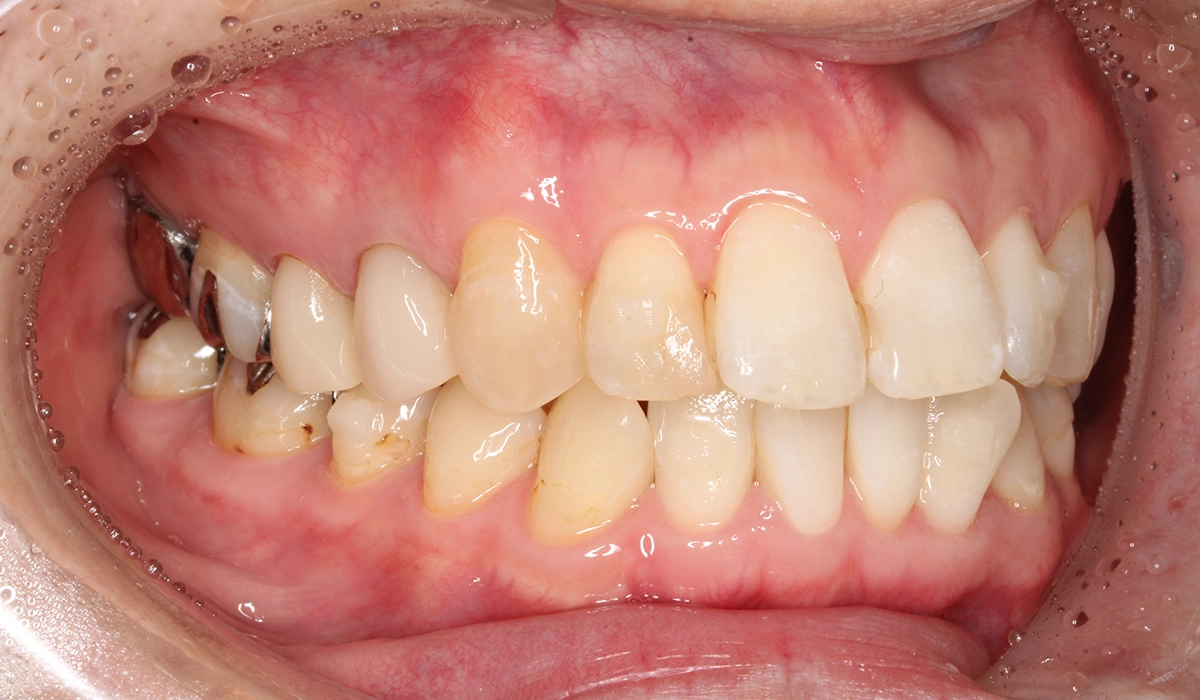

術前:右側

術後:右側